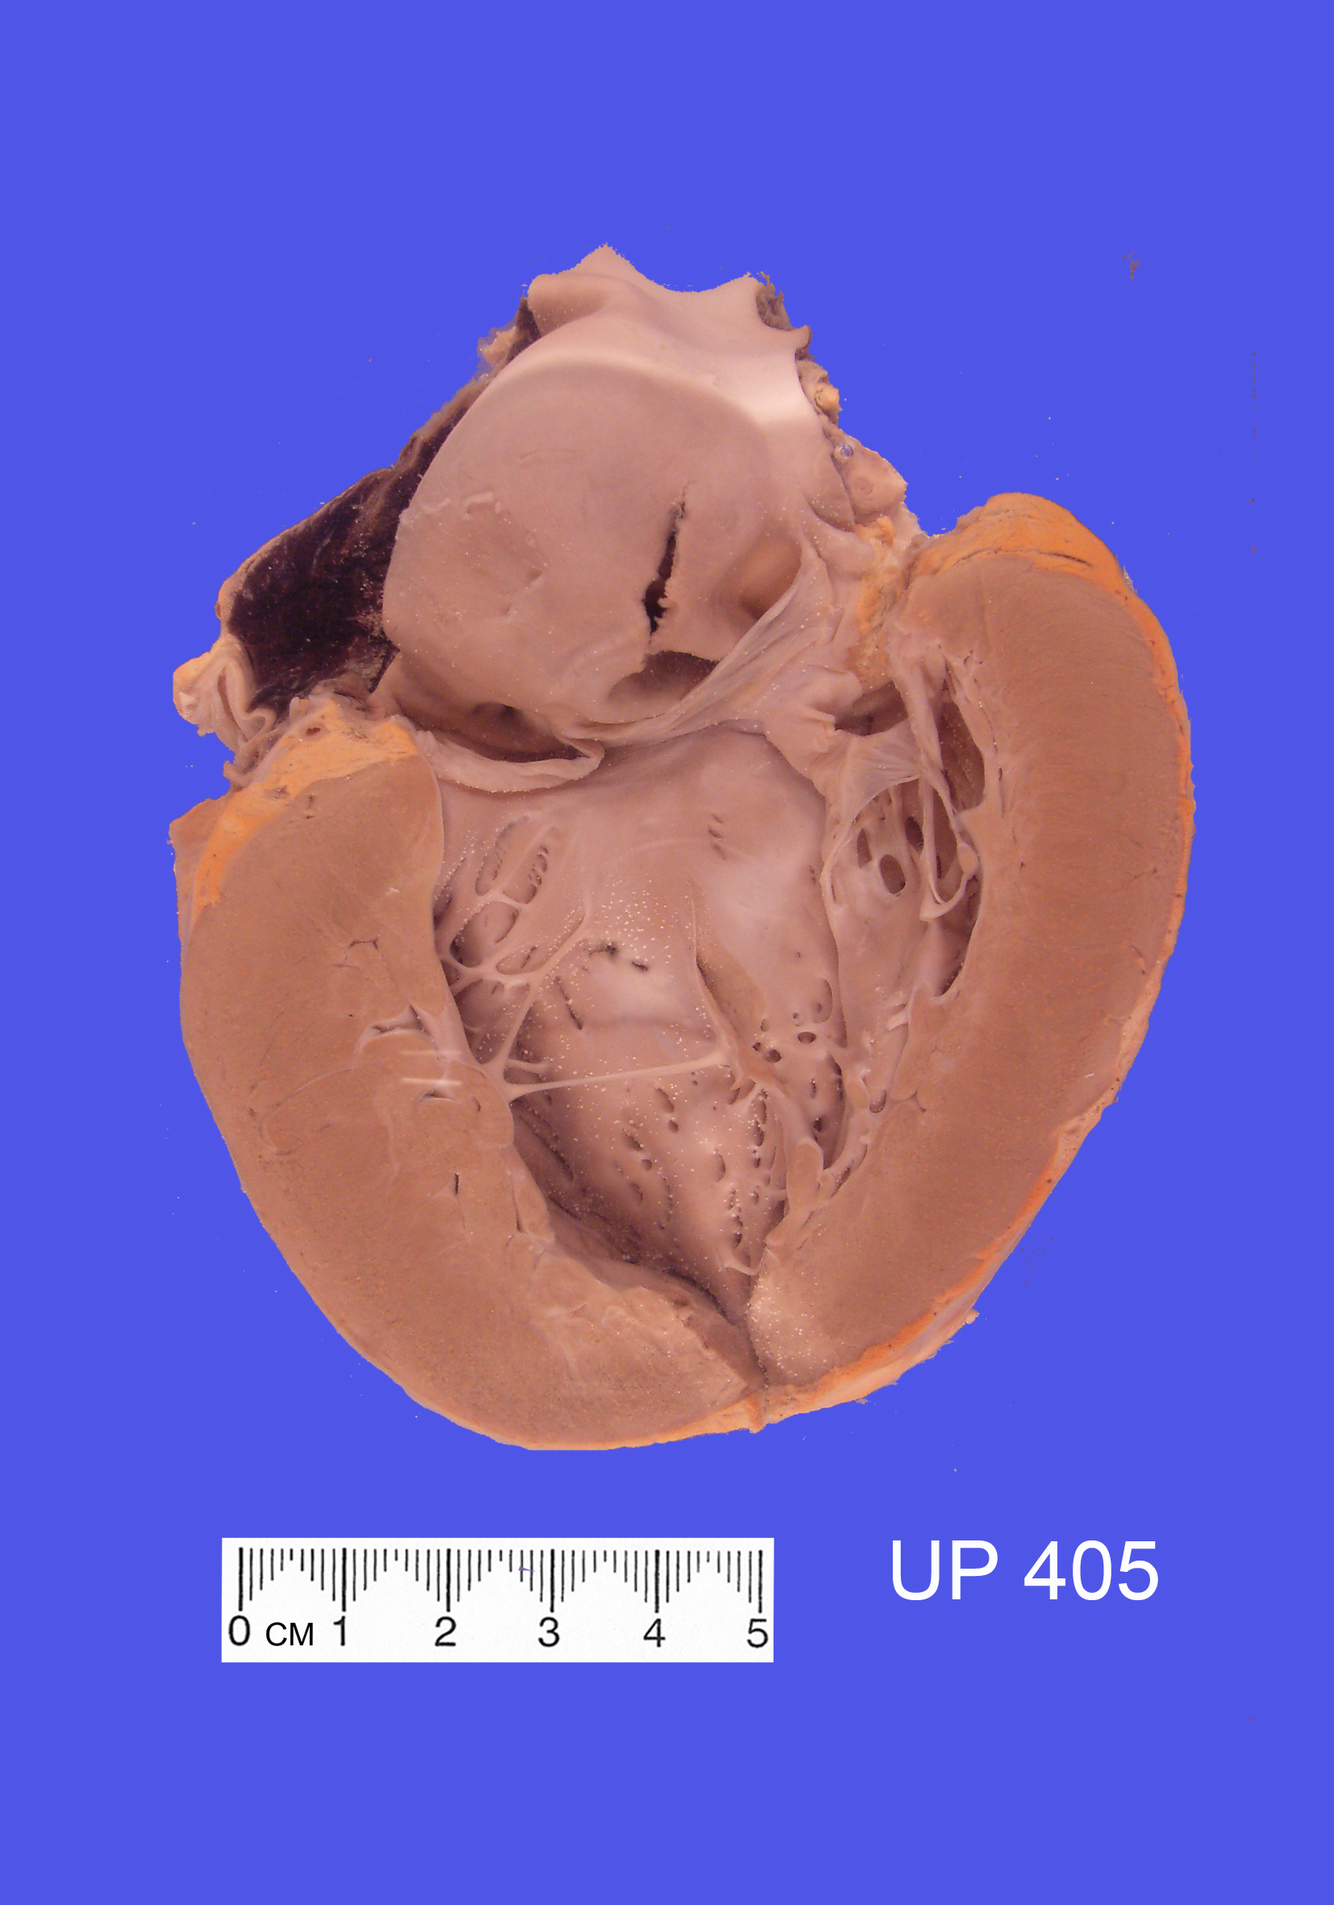

The specimen shows a slice through the left and right ventricles.

A massive recent infarct is present in the anterior, septal and posterior regions of the left ventricle with a slight extension onto the posterior wall of the right ventricle. The necrotic muscle appears pale yellow-grey in colour and reactive hyperaemia is seen at the interface with the viable myocardium. This is the territory of the left anterior descending coronary artery.

A mural thrombus has formed on the anteroseptal infarcted zone.

The anterior and posterior descending coronary arteries can be seen in cross-section in the epicardial fat and they are severely stenosed by atherosclerosis.

Histological sections confirmed a recent infarct, only days old, with loss of cardiac muscle nuclei and intense hyperaemia bordering the infarct.

The postmortem also revealed numerous peripheral pulmonary emboli with an occasional associated infarct and a left calf deep venous thrombosis. A small recent infarct was also present in one kidney.